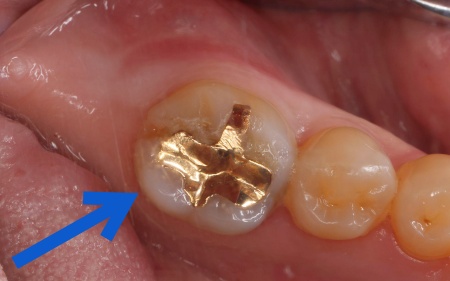

まず根管を丁寧に洗浄・消毒し、MTAセメントを用いて根の先端まで隙間なく密封しました。

その後、被せ物を装着するために歯の形を整え、型取りを行っています。

診断結果をお伝えした上で、再度根管治療を行ってから、殺菌効果の高いMTAセメントを用いて根管をしっかりと封鎖し、その後ジルコニアクラウンで修復する治療計画を提案し、同意いただきました。